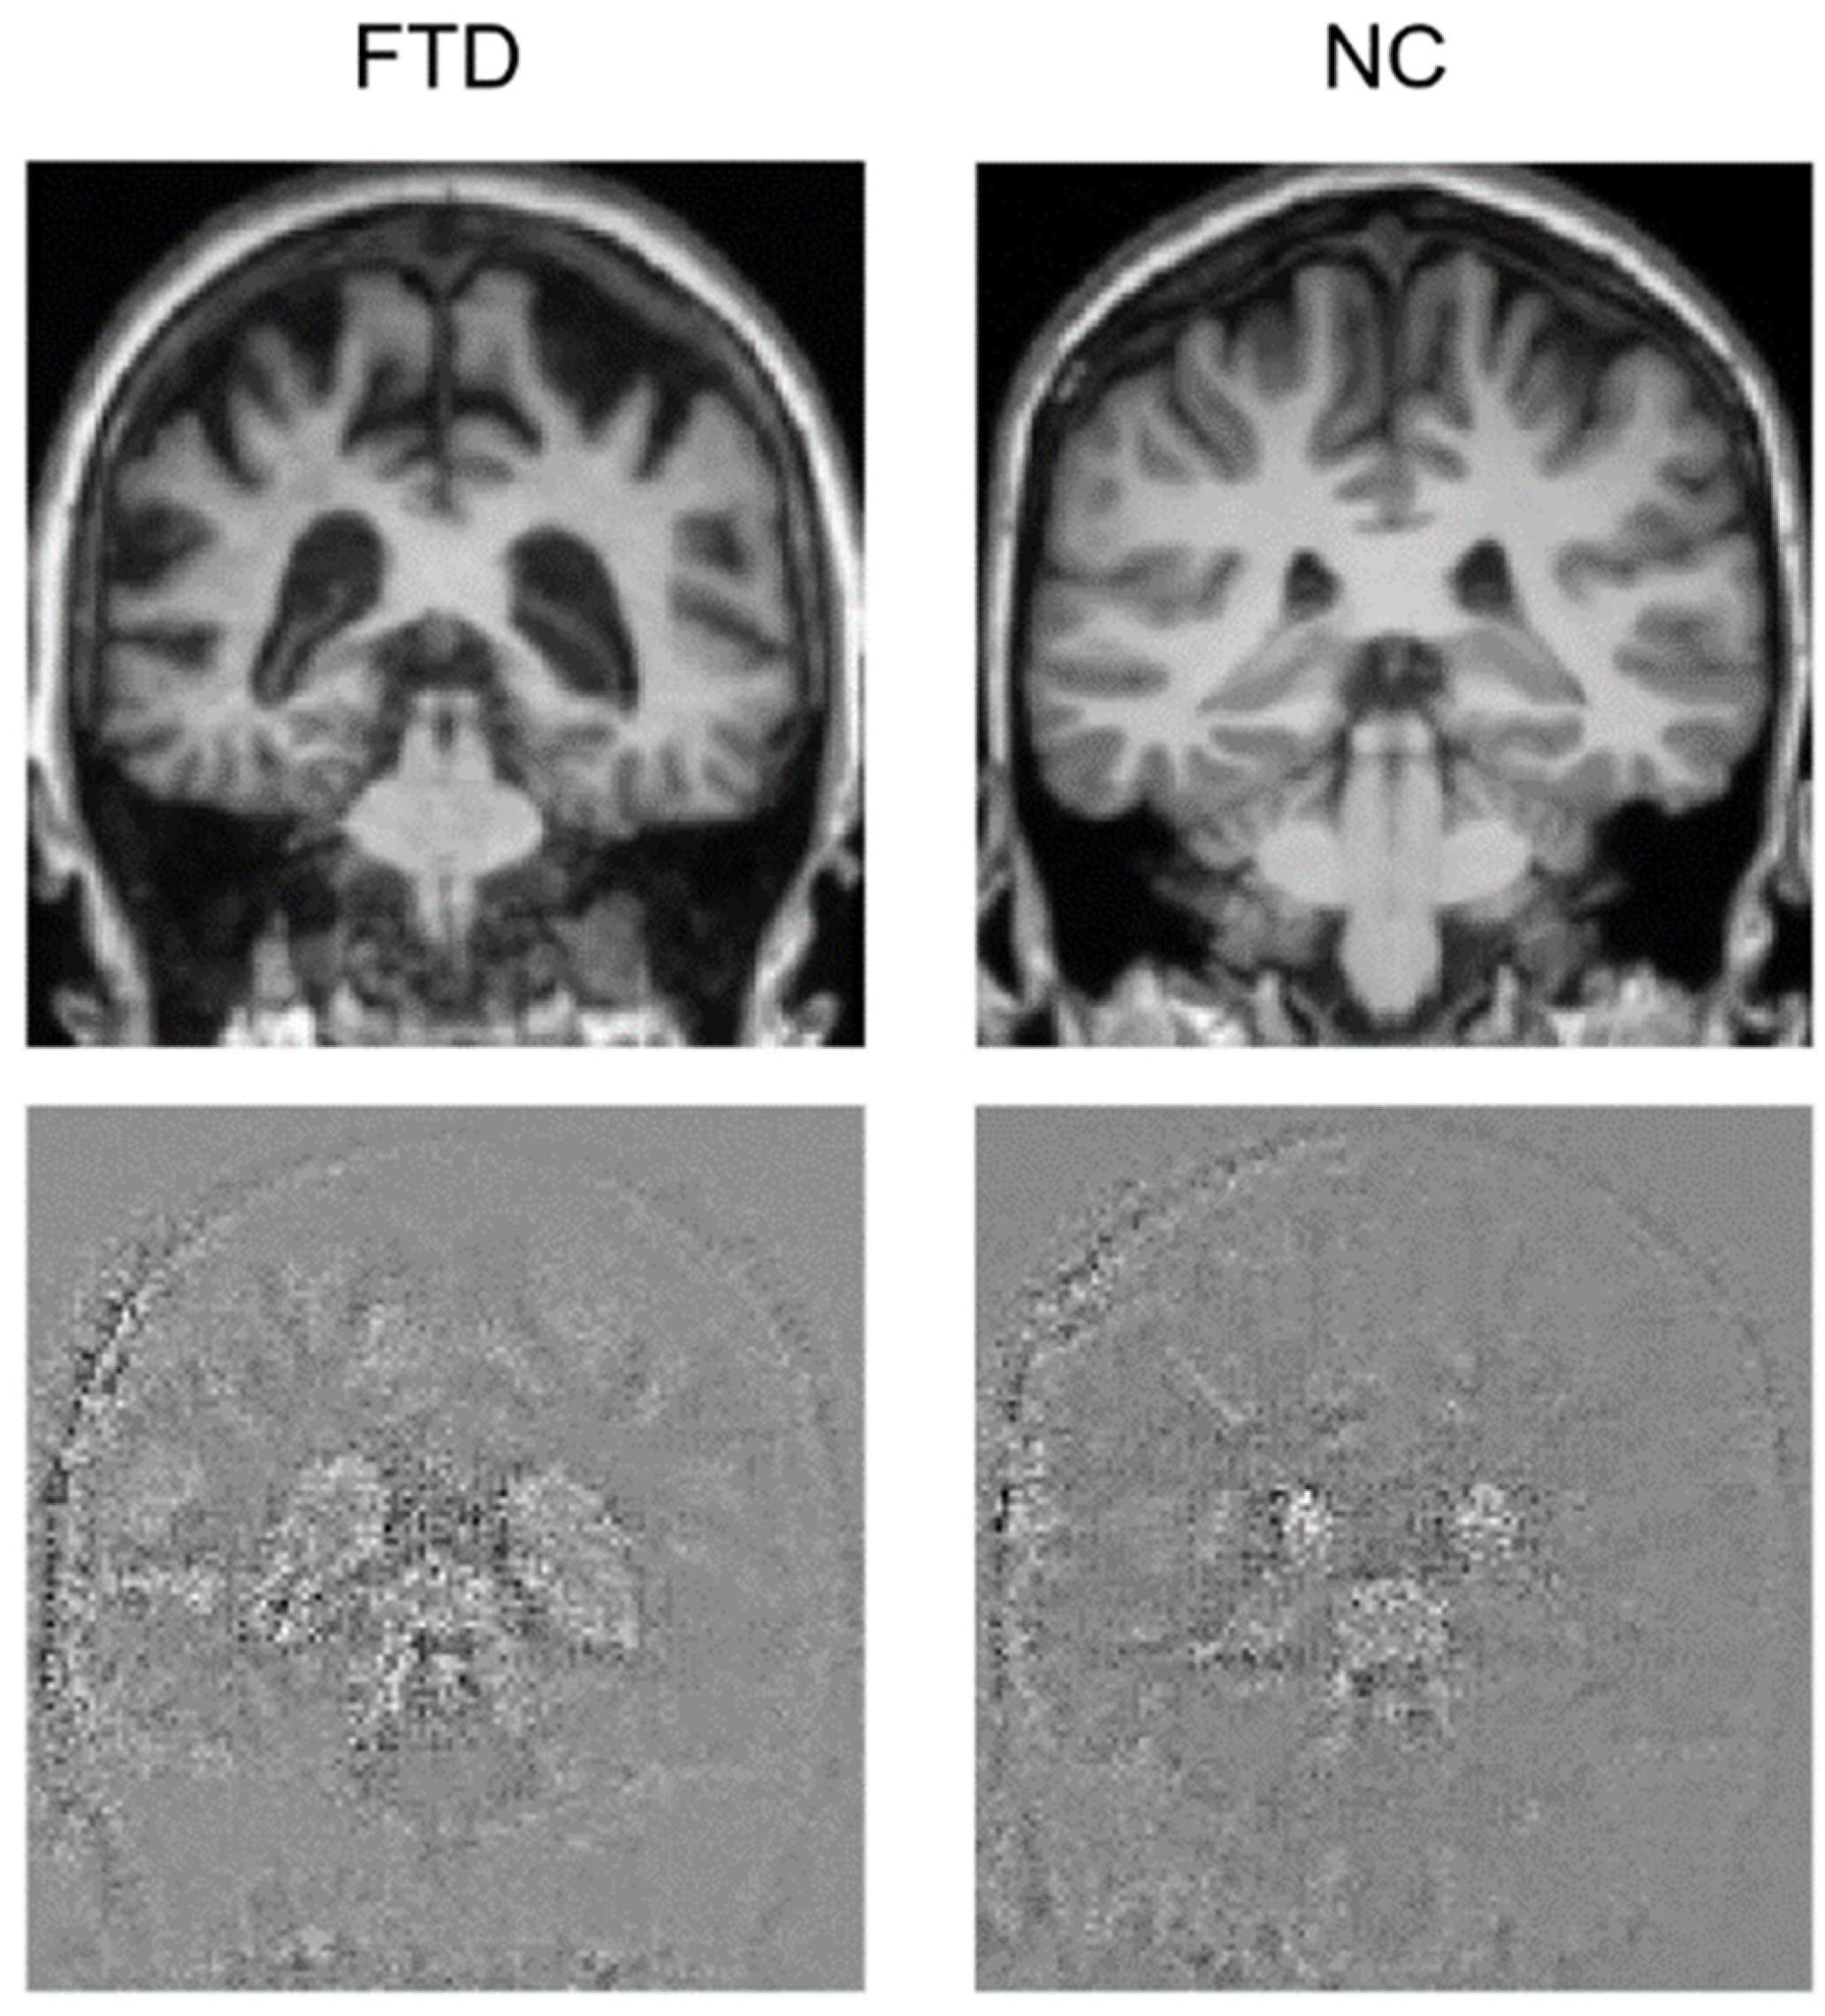

2.9. Explainable AI Using the Attention Map Method

3.3. Attention Maps